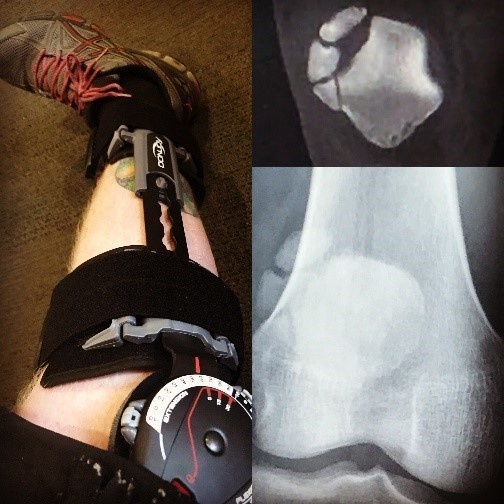

Pfc. Joshua Berry’s knee at the beginning of physical therapy on March 15th at the Evans Community Hospital Fort Carson, Colorado. (Photo Courtesy Pfc. Joshua Berry)